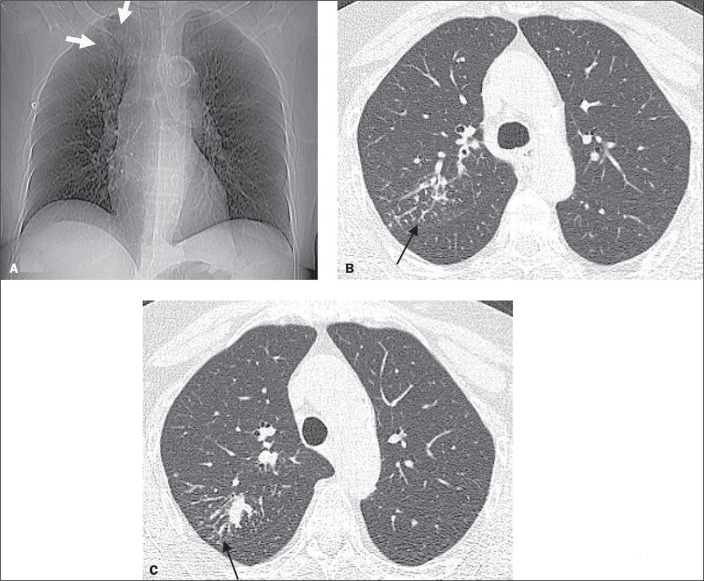

Although kidney transplantation is the best therapeutic option for patients with chronic kidney disease, the immunosuppression required greatly increases susceptibility to infections that are responsible for high post-transplant mortality. Pulmonary tuberculosis (TB) represents a major cause of such infections, and its early diagnosis is therefore quite important. In view of that, we researched the manifestations of active pulmonary TB in kidney transplant recipients, through chest X-ray and computed tomography (CT), as well as determining the number of cases of active pulmonary TB occurring over a 3.5-year period at our institution. We identified four cases of active pulmonary TB in kidney transplant recipients. The CT scans provided information complementary to the chest X-ray findings in all four of those cases. We compared our CT findings with those reported in the literature. We analyzed our experience in conjunction with an extensive review of the literature that was nevertheless limited because few studies have been carried out in lowand middle-income countries, where the incidence of TB is higher.